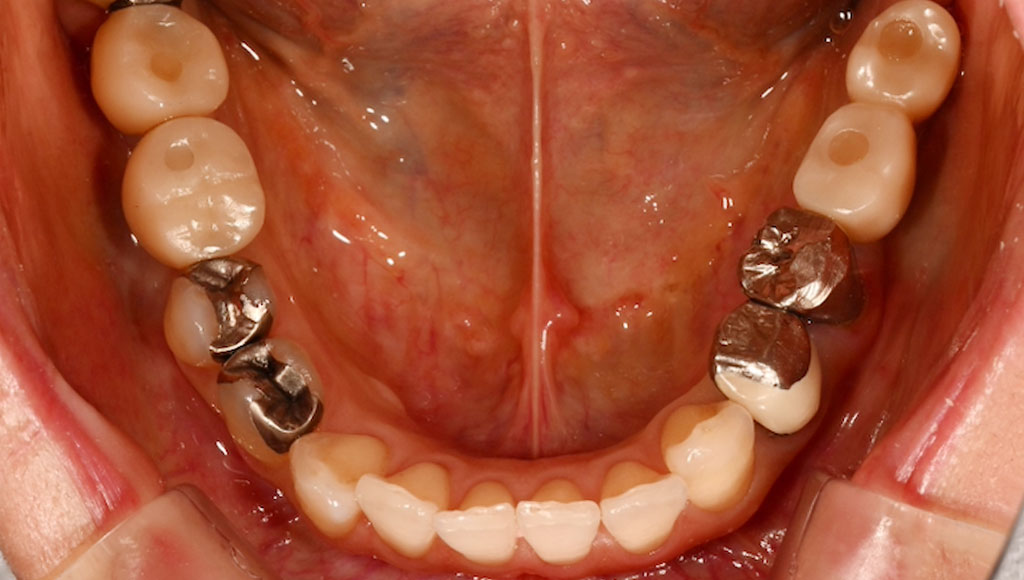

小臼歯(左下45番、右下45番)ジルコニアクラウンによる審美治療

Before1

After1

Before2

After2

患者様の主訴

50代女性。横浜市在住。左下45番、右下45番の奥歯の銀歯が見た目に気になりご来院。

診断結果

左下45番、右下45番のインレーを外し、歯の形成を行いジルコニアクラウンをセット

治療内容

ジルコニアクラウンを装着するために元のインレーを外し、歯の形成を行い光学印象(プライムスキャンによる)型取りを行いました。光学印象のデータを元に当院の院内技工室にてデジタル加工を行い、ジルコニアクラウンを作成し、セットを行いました。

治療期間

2回

治療費用

総額:440,000円(税込)

◼️内訳

ジルコニアクラウン:110,000円(税込)/1本×4本

光学印象(プライムスキャン)

リスク・副作用

補綴物の脱落・欠落、咬合違和感、色調補正